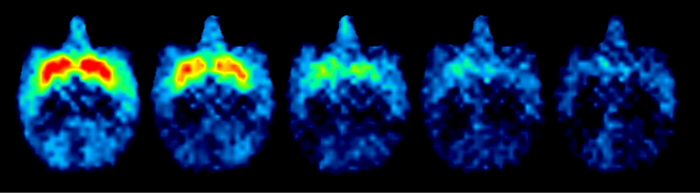

In their study, the researchers first trained the animals to perform “reward size” tasks and “work/delay tasks.” These tasks allowed them to measure how perceived reward size and required effort influenced the task-performing behavior. Dr. Takafumi Minamimoto, the corresponding author of the study explains, “ We systematically manipulated the D1R and D2R of these monkeys by injecting them with specific receptor-binding molecules that dampened their biological responses to DA signaling. By positron emission tomography-based imaging of the brains of the animals, the extent of bindings or blockades of the receptors was measured .” Then, under experimental conditions, they offered the monkeys the chance to perform tasks to achieve rewards and noted whether the monkeys accepted or refused to perform the tasks and how quickly they responded to the cues related to the tasks.